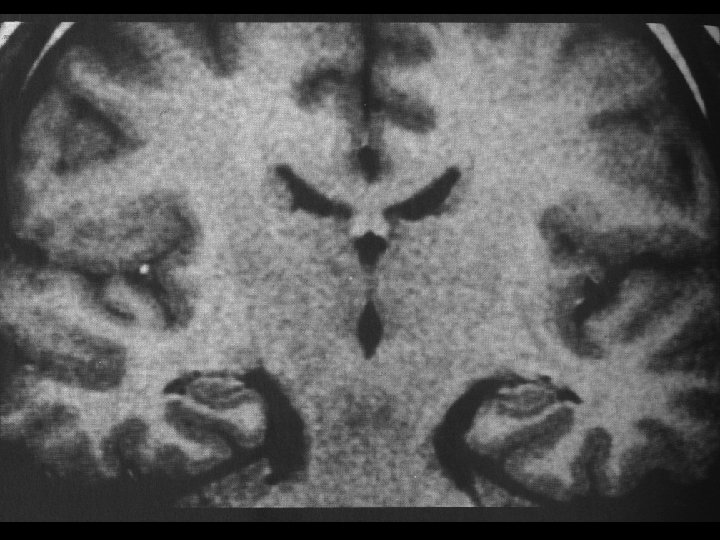

Multi Sensory Information About Spatial Memory is Only Brought Together in the CA 1 Region of the Hippocampus

The Hippocampal Pyramidal Cells Encode a Cognitive Map of Space : Is Attention Importand for Formation of the Map or for its Perpetuation